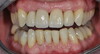

Restauration complète maxillaire et mandibulaire

Eclaircissement et couronnes céramo-céramiques